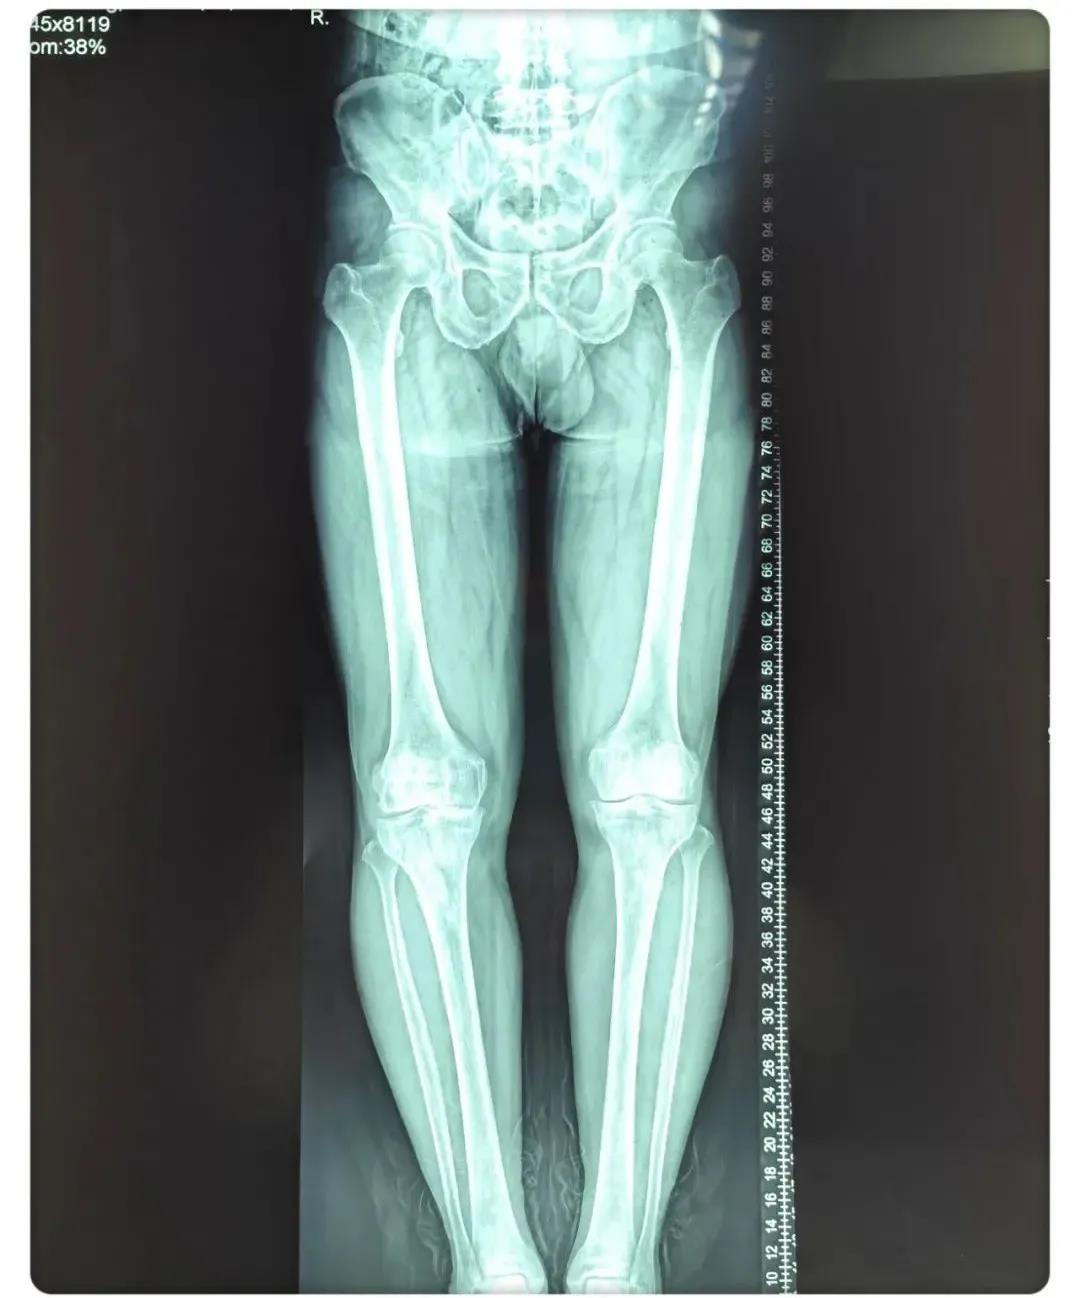

術(shù)前患者腿部X線片